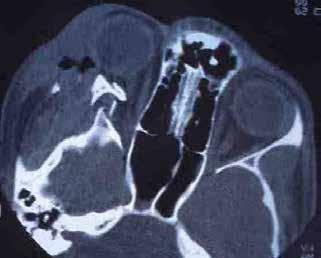

Figure 3. Multimodal imaging of a male diabetic patient affected by PDR and DME that has already been treated by incomplete laser photocoagulation therapy. 3A) UWF pseudocolor retinography displaying hard exudates and intraretinal hemorrhages within vascular arcades and peripheral laser photocoagulation therapy; 3B) UWF SS-OCT showing focal center-involving DME; 3C) Late phase UWF FA (describing mild BRB disruption with 2 leakage areas compatible with NV along inferior vascular arcade; 3D) 15x15 En-face WF-SS-OCTA presenting FAZ enlargement, diffuse capillary drop-out and temporal mid-peripheral retinal nonperfusion areas, and two pathological vascular networks associated to NVs.